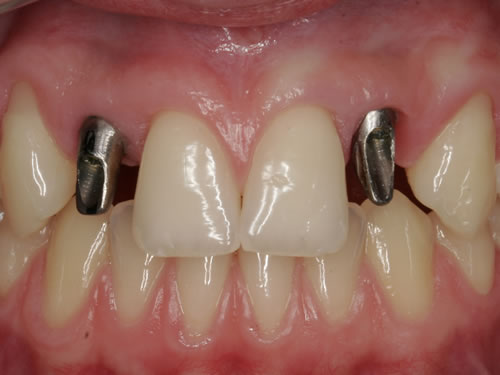

Eine besondere Herausforderung ist die Oberkieferfrontzahnregion. Der Wunsch nach einem perfekten Resultat ist geradezu selbstverständlich. Jeder möchte große, weiße Zähne und ein gesundes, reizloses Zahnfleisch besitzen (Abb. 3.30).

Abb. 3.30: Perfektes Resultat einer Versorgung.

Im Alter von 12 Jahren hatte ein jetzt 20-jähriges Mädchen durch einen Skateboardunfall zwei Schneidezähne im Oberkiefer verloren (Abb. 3.33). Zunächst wurden die Zähne wieder eingesetzt, doch nach 2 Jahren lösten sich die Wurzeln auf und mussten entfernt werden (Abb. 3.34). Damit das Mädchen nicht ohne Zähne herumlaufen musste, wurden beide Frontzähne durch eine kleine Prothese ersetzt (Abb. 3.35). Das Mädchen hat die Prothese ohne zu klagen regelmäßig getragen. Inzwischen sträubt sie sich allerdings gegen diesen herausnehmbaren Zahnersatz, da sie einen Freund gefunden hat und ihr das Tragen der Prothese jetzt unangenehm ist. Die Lücke wurde durch 2 Implantate und Einzelkronen geschlossen (Abb. 3.36).

Gesunde Zahnsubstanz kann aber geschont werden, wenn die Einpflanzung einer künstlichen Zahnwurzel möglich ist. In bestimmten Fällen kann dies bereits nach dem 14. Lebensjahr erfolgen. Das gilt für den unfallbedingten Zahnverlust (Abb. 3.22 bis 3.36), aber auch für die von der Natur nichtangelegten bleibenden Zähne (Nichtanlagen) (Abb. 3.37 bis 3.39).